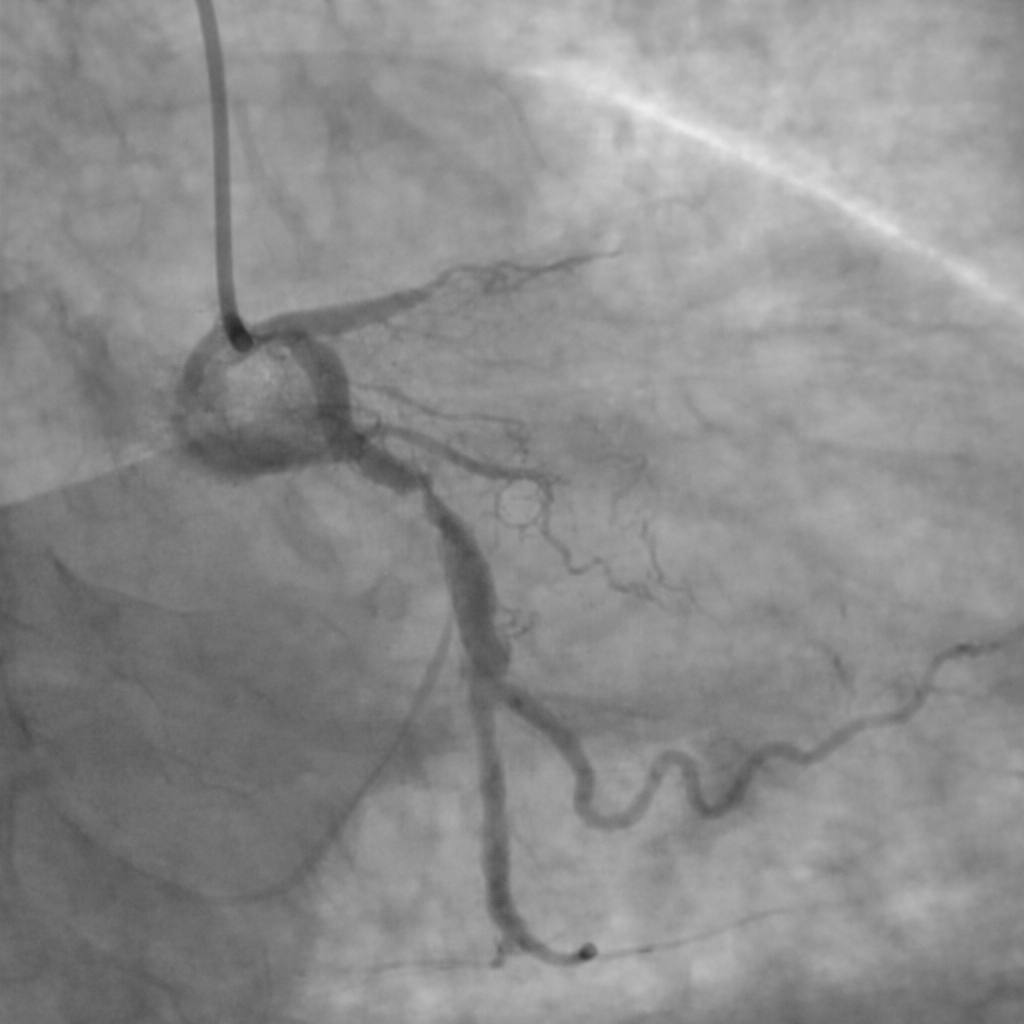

Cardiologul din Târgoviște, dr. Țoni Ovidiu, subliniază pericolele asociate cu nerespectarea tratamentului la pacienții cu stenturi implantate. Potrivit damboviteanul.com, medicul avertizează că un stent nu este o soluție definitivă și că întreruperea medicației poate duce la complicații grave, inclusiv infarct miocardic.

Dr. Țoni Ovidiu explică faptul că stenturile pot deveni obstruate. Acesta a exemplificat prin cazul unui pacient care a suferit un infarct miocardic acut, în ciuda faptului că avea stenturi implantate de mai mulți ani. „Din păcate, a decis să-și administreze medicația din când în când”, a declarat medicul.

În astfel de cazuri apare stenoza intrastent, o îngustare a arterei în interiorul stentului, care poate fi cauzată de proliferarea țesutului sau de tromboza de stent, provocată direct de întreruperea tratamentului antiagregant.

„Implantarea unui stent nu înseamnă vindecare definitivă. Medicația trebuie luată zilnic, corect și pe termen lung”, avertizează dr. Țoni Ovidiu. El reamintește pacienților că controalele cardiologice regulate sunt esențiale și subliniază: „Stentul funcționează atât timp cât pacientul își face partea lui.”